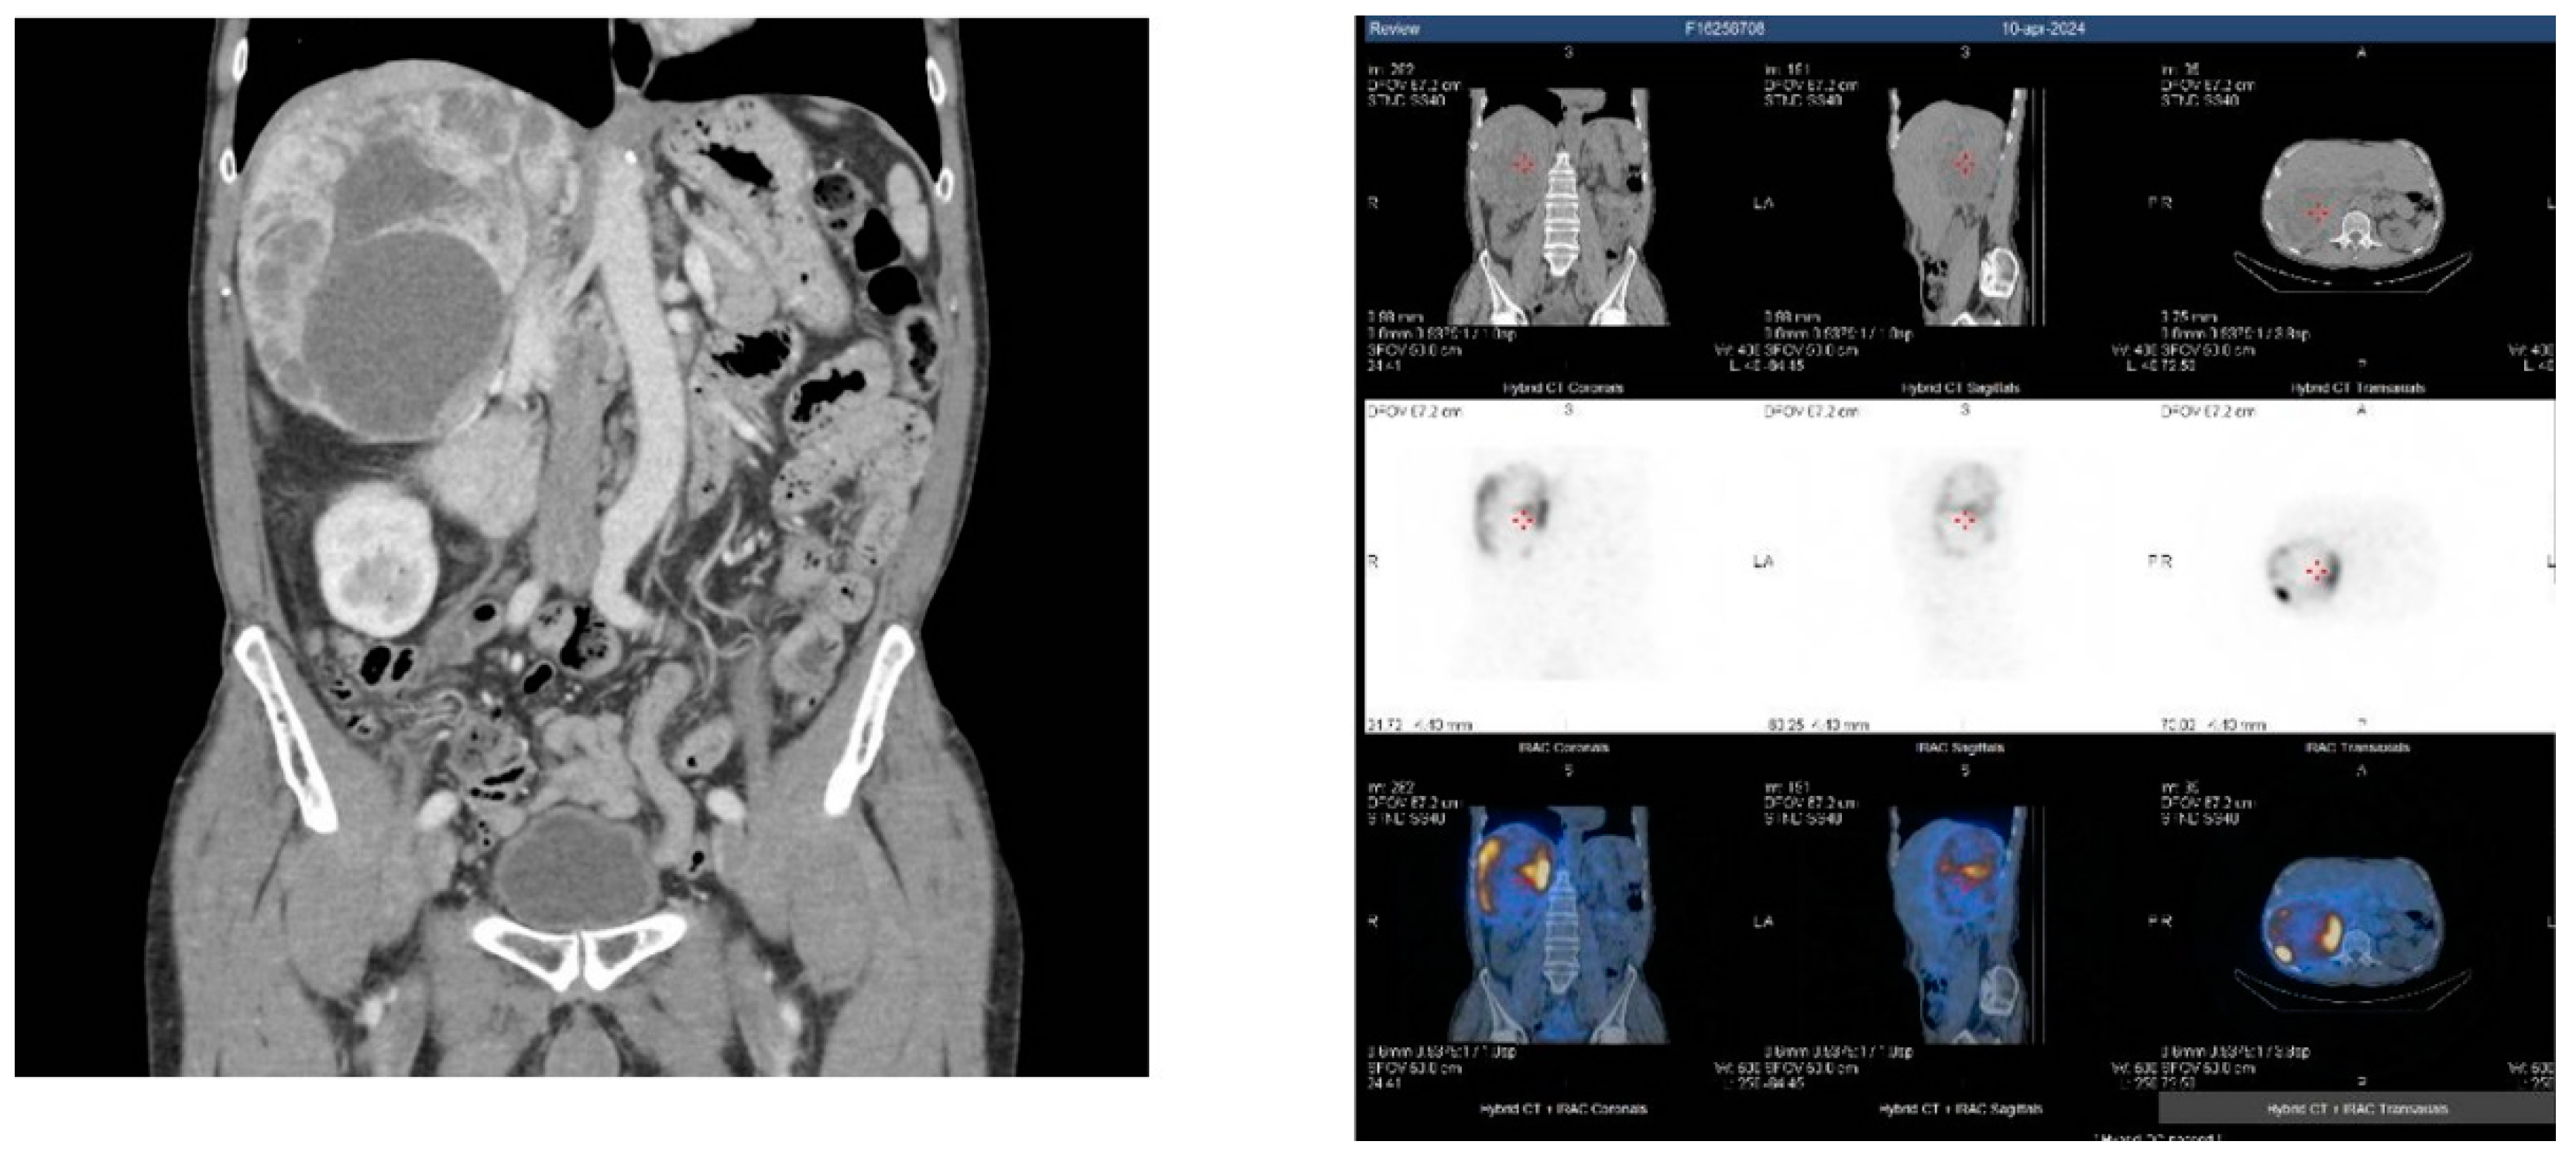

- Extra-adrenal localization is most often genetically determined, so in the pre-surgery management, we need to be sure that we are not dealing with a disease with multiple localizations, considering also the thorax and head and neck compartment.

- Extra-adrenal localization is more typical for cluster-1 PGLs, while adrenal tumors belong mostly to cluster-2, so in the choice of functional imaging, there is no doubt in preferring [68Ga]-DOTA-SSA PET/CT for extra-adrenal tumors and [18F] FDOPA PET/CT for adrenal tumors.